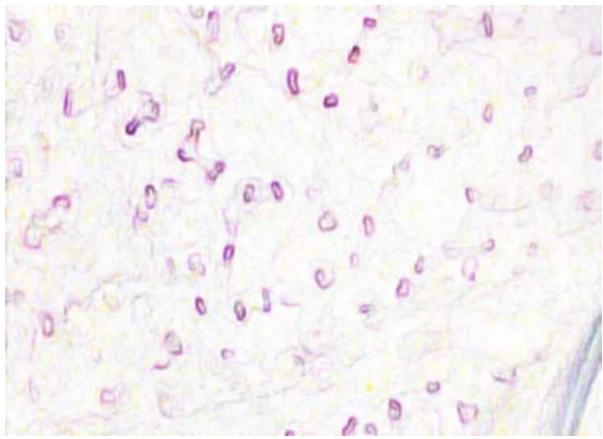

Recent advances in digital imaging, e.g., increased number of pixels captured, have meant that the volume of data to be processed and analyzed from these images has also increased. Deep learning algorithms are state-of-the-art for analyzing such images, given their high accuracy when trained with a large data volume of data. Nevertheless, such analysis requires considerable computational power, making such algorithms time-and resourcedemanding. Such high demands can be met by using third-party cloud service providers. However, analyzing medical images using such services raises several legal and privacy challenges and do not necessarily provide real-time results. This paper provides a computing architecture that locally and in parallel can analyze medical images in real-time using deep learning thus avoiding the legal and privacy challenges stemming from uploading data to a thirdparty cloud provider. To make local image processing efficient on modern multi-core processors, we utilize parallel execution to offset the resourceintensive demands of deep neural networks. We focus on a specific medical-industrial case study, namely the quantifying of blood vessels in microcirculation images for which we have developed a working system.